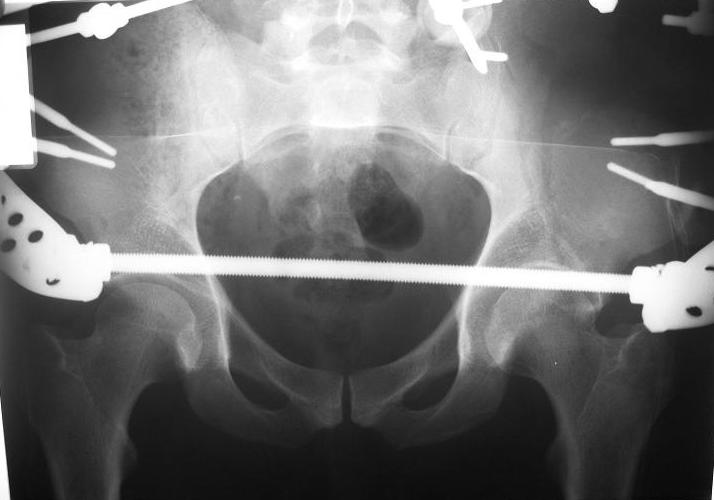

Перелом таза

Поступил пациент после кататравмы (упал с высоты 4м). После обследования установлен Ds: Сочетанная травма. ЗТГК перелом 5-6 ребер справа. Ушиб левого леогкого. Оскольчатый перелом крыла подвздошной кости слева, со смещением. в экстренном порядке выполнена операция о/синтез таза стержневым аппаратом. Снимки прилагаются. Пациент со 2-го дня стал ходить без костылей. Из анамнеза жизни у пациента имеется гепатит В и С, с 1998г. употребляет наркотики (героин 1г в день нормальная доза). На контрольных снимках таза в аппарате смещение отломков сохраняется, да еще и стержни сломались. Подскажите ув.коллеги, как поступить в данной ситуации: оставить все как есть или добиваться репозиции в аппарате, или планировать на открытую репозицию. На сегодняшний день пациент стабилен, по анализам компенсирован. Принимает героин по другому справиться не может. С ув. Андрей